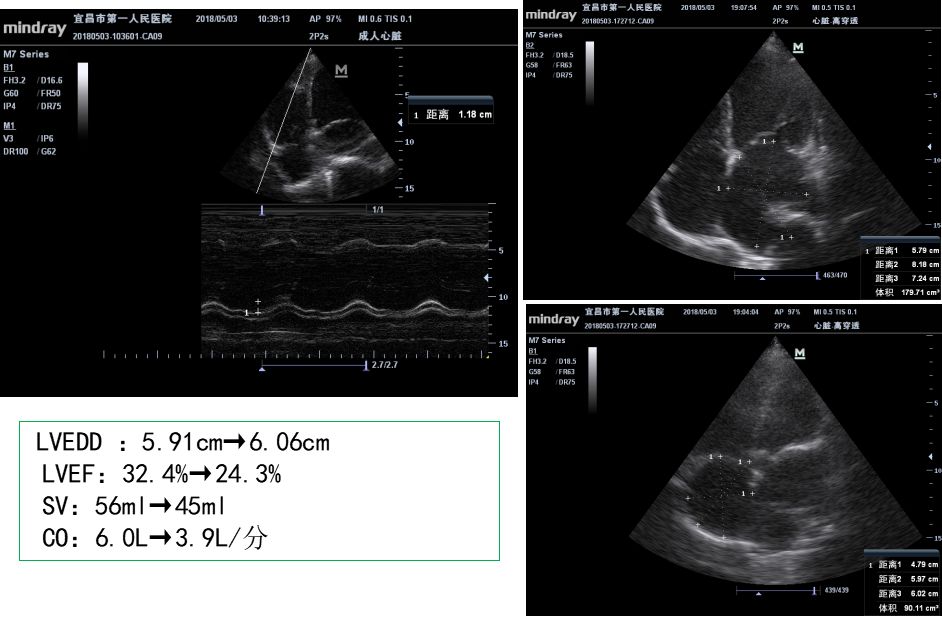

心功能进一步恶化:LVEF进行性下降

LVEF 由30%恢复到35%,心功能恢复并不明显,而由心血管给予利尿、扩血管治疗后,病史中并没有对病人心功能的详细评估,肺部感染情况也没有交代,这就给病人回家后再次出现严重心衰埋下了隐患。所以病人在家期间出现间断咳嗽、胸闷,再次出现严重心衰(左室短轴缩短率16.3%,LVEF:32.4%,左房增大:4.21cm,左室增大:5.91cm),提示左心功能不全,心源性休克。按照2018中国心衰诊断和治疗指南的标准,是射血分数降低的心衰,符合围生期心肌病的诊断。